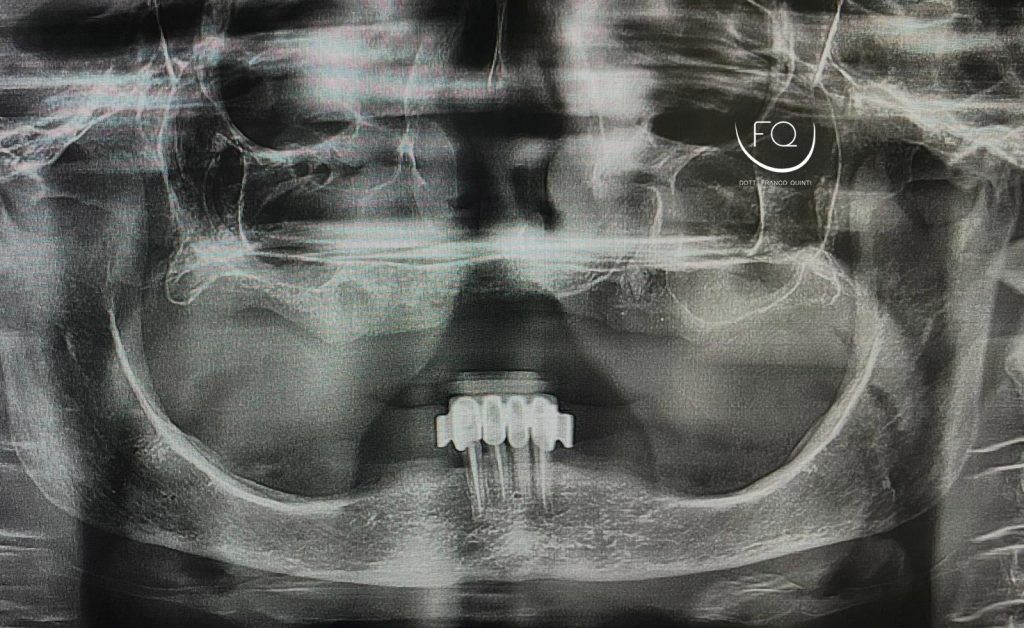

Il trattamento ha previsto l’inserimento di 4 impianti Prama Power di Sweden & Martina e la contestuale riabilitazione protesica provvisoria. Tra 3 mesi il caso verrà finalizzato con una protesi definitiva.